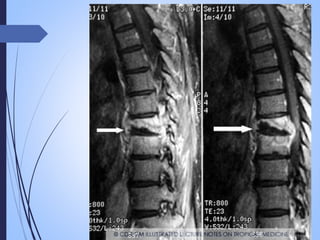

Radiologia

 Formas adenopatías: la presencia de adenopatias hiliares o

mediastınicas es el hallazgo radiológico mas frecuente en la TB

pediátrica

 Formas cavitadas

 Una sola lesión

 Nódulo pulmonar

 Lesiones tuberculosas

cavitadas

AFECTACION TB A

NIVEL CEREBRAL